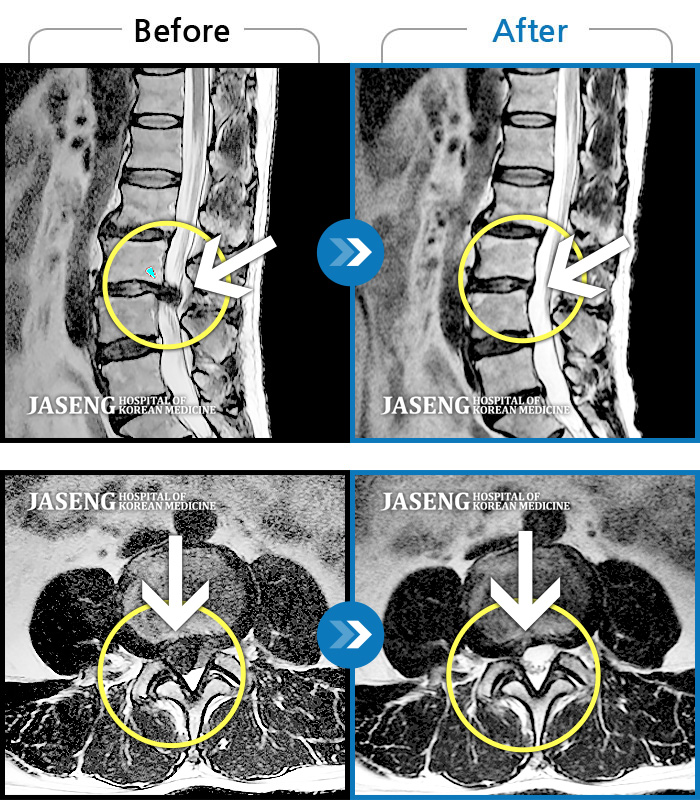

허리디스크

보라매 · 신원준 원장

우측 다리가 저리고 감각이 둔함

촬영시기

2019.04.11 ~ 2019.11.19

2020.01.16